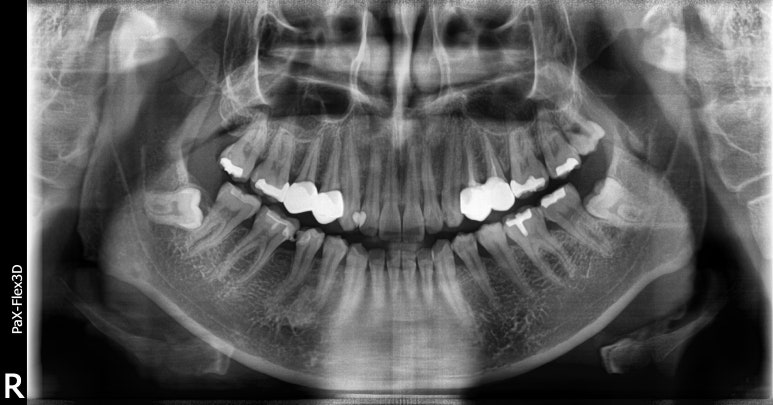

정확한 진단을 위해 파노라마 엑스레이와 CT를 촬영해보니 잇몸에 염증이 다소 있는 것을 확인했습니다.

해당 치아는 이미 신경치료 후 크라운을 씌운 후 사용하던 치아라 이미 염증이 생겼다면 발치가 불가피한 것으로 판단했습니다.

그래도 환자분은 잇몸에 염증은 있지만 심하지는 않아서 내원하신 당일 발치즉시임플란트 수술 진행했습니다.

다만, 잇몸뼈가 다소 녹아있어 당일식립하면서 뼈이식도 함께 진행해주었습니다.